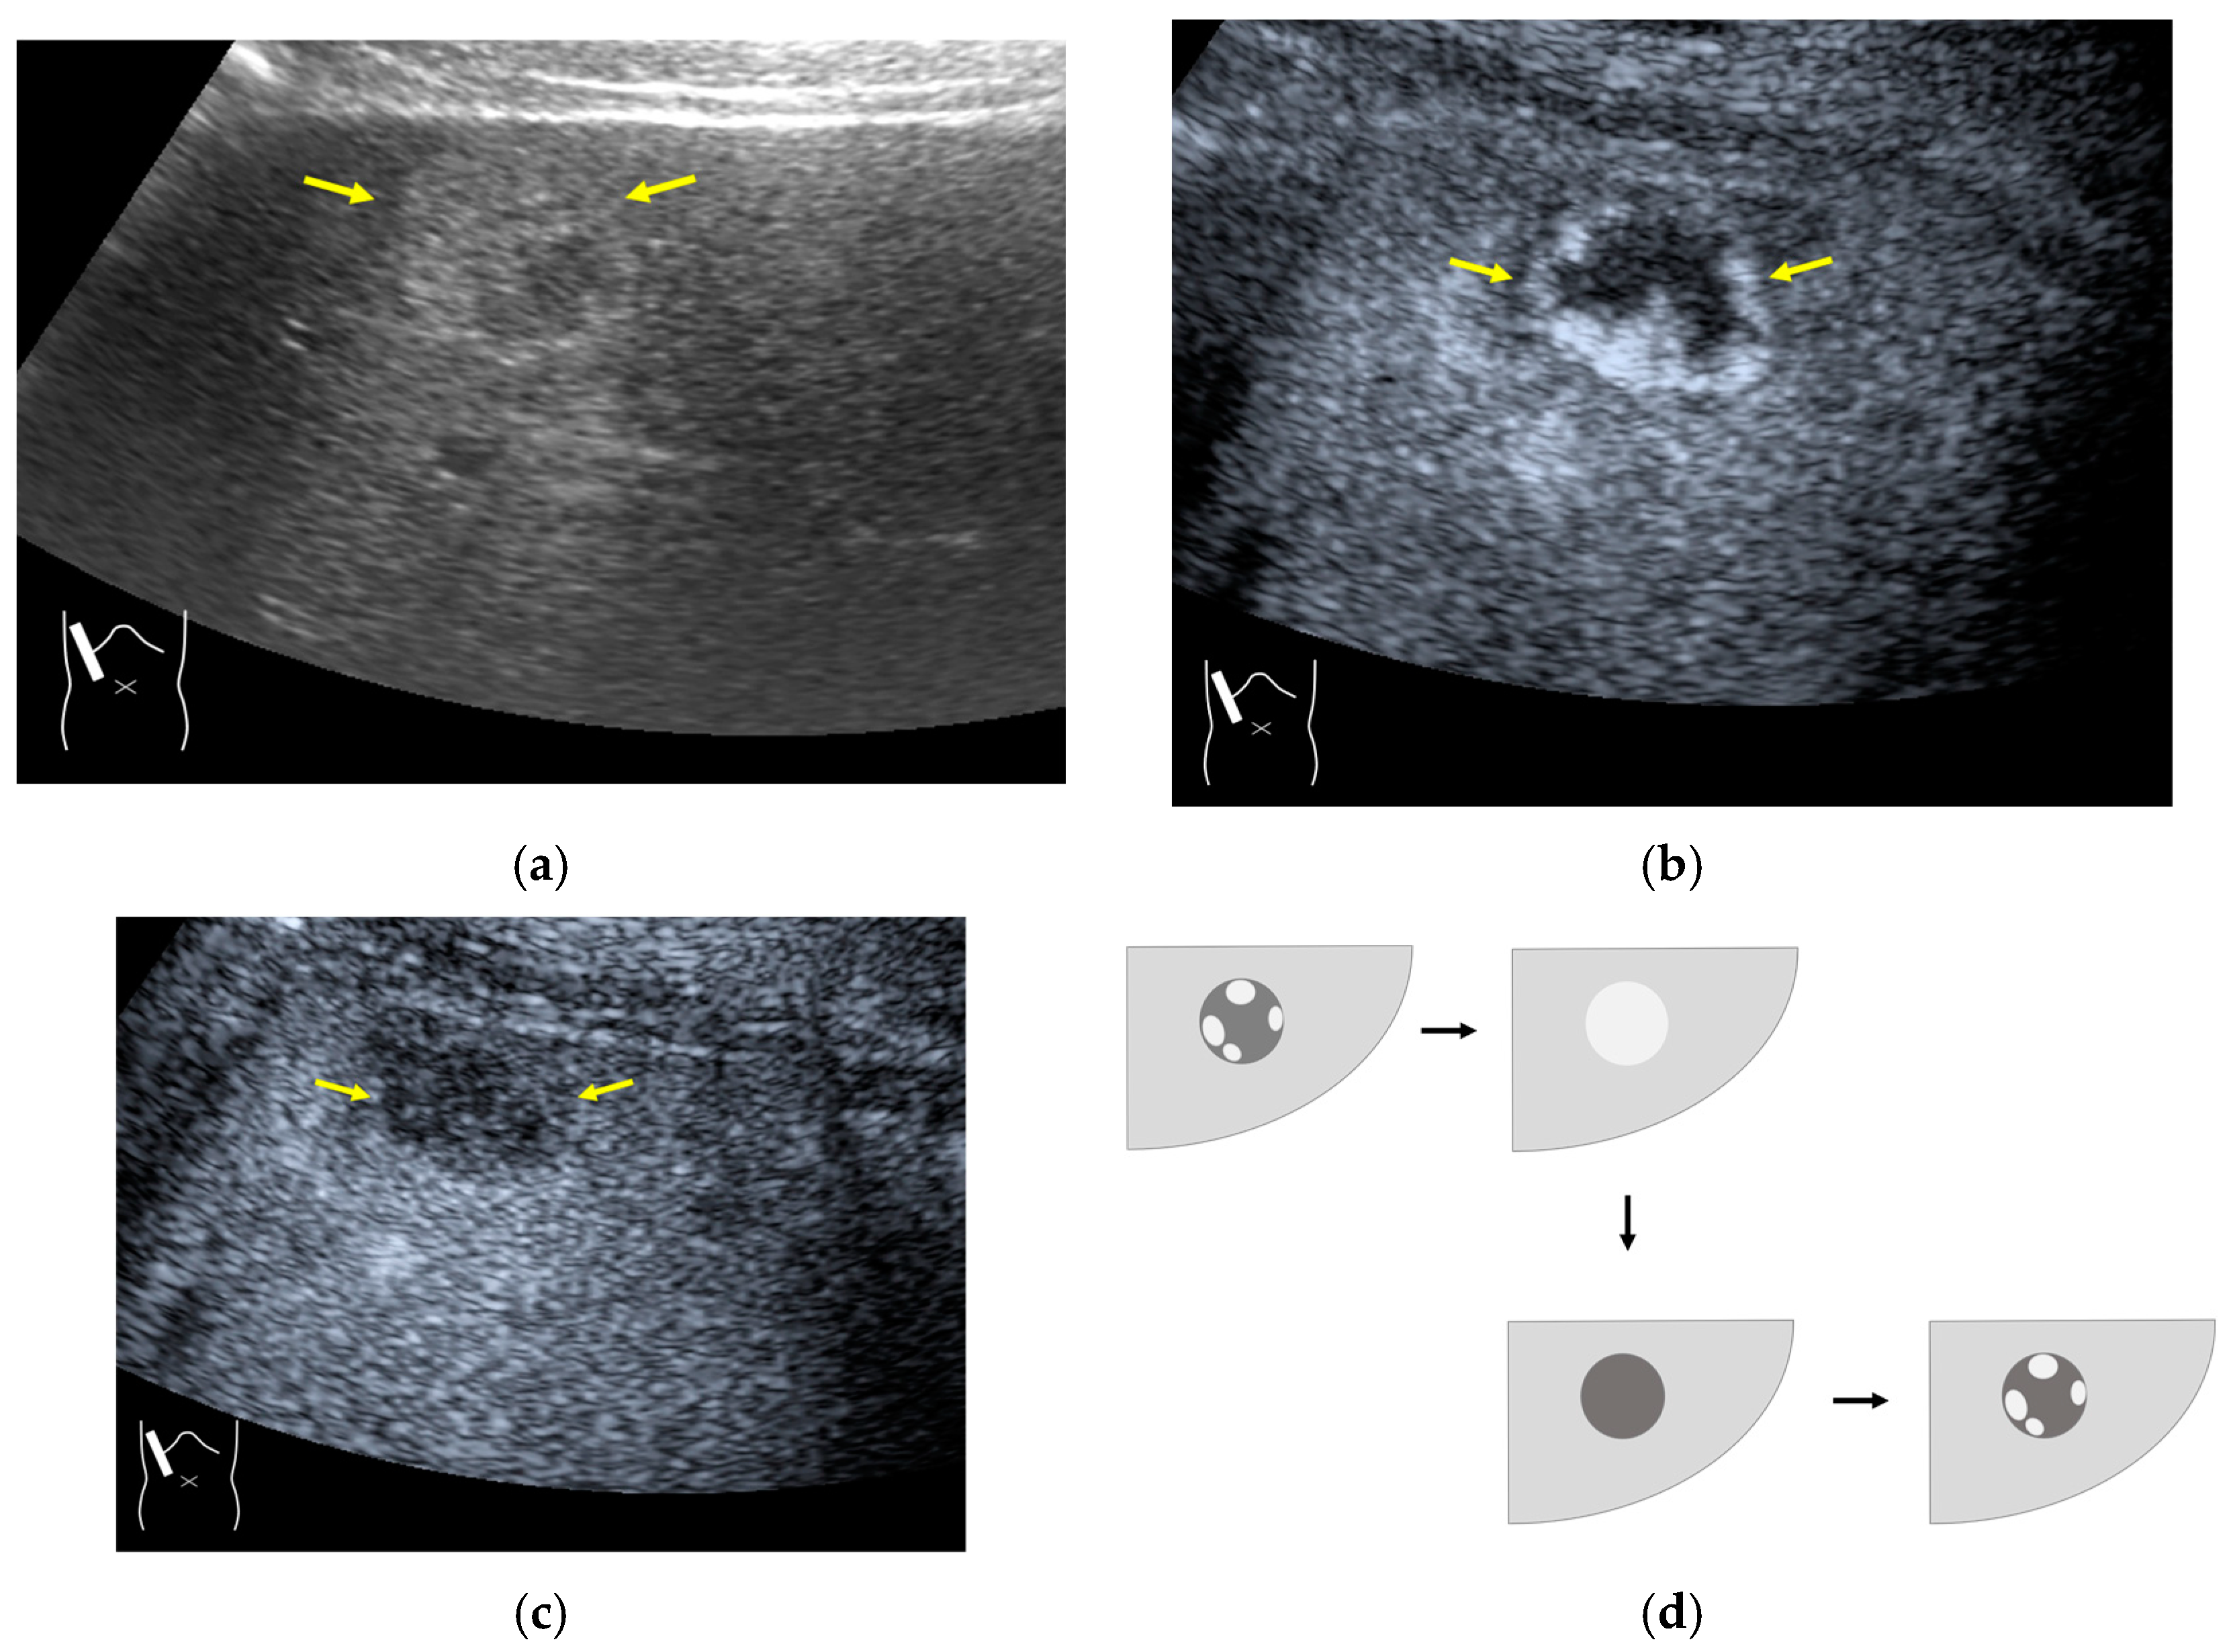

3.2.1. Microbubble Destruction Artifacts

Microbubble destruction occurs during daily CEUS examinations in all phases, even under the optimal settings. The most representative example is a microbubble destruction artifact seen at the hepatic surface (Figure 11). Thus, it is important to understand that inappropriately increased microbubble destruction occurs in the case of continuous CEUS examination, even under optimal settings. Bubble destruction artifacts cause a delicate diagnostic problem, especially when evaluating the degree of wash-out. Generally speaking, the degree of microbubble destruction differs from area to area depending on the blood flow velocity. We encounter this problem most frequently in hemangioma, where destroyed microbubbles are not quickly replaced in intrahemangioma sinusoids because of the low blood flow velocity within them [53], while destroyed microbubbles can be quickly replaced in the surrounding hepatic parenchyma (Figure 12). This phenomenon causes the important diagnostic problem of mimicking a malignant lesion. According to the CEUS LI-RADS 5) classification, the presence of wash-out in the later phase suggests the diagnosis of a malignant tumor in more than 90% of cases [2,11,12,13,14,15,16]. The simplest prevention strategy is the “re-injection” of a contrast medium [54], which enables us to observe the target lesion in all phases once more, from the arterial phase until the later phase, with intermediate scanning interruptions.

Figure 12.

Manhole-like defect in hemangioma: (a) gray-scale US of the case (arrows: hemangioma); (b) CEUS shows a cotton wool appearance in the periphery of the lesion (arrows): (c) the lesion shows a complete defect in the lesion during observation (arrows); (d) a reasonable explanation of this phenomenon. In hemangioma, destroyed microbubbles are not quickly replaced because of the low blood flow velocity, mimicking a wash-out phenomenon.